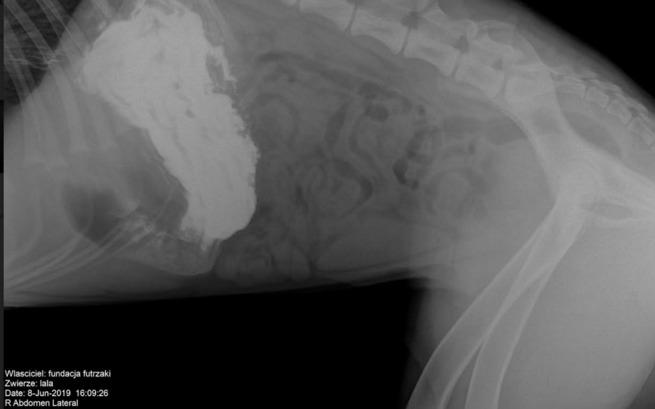

Lena we wtorek została przewieziona na dom tymczasowy, w piątek pojawiły się wymioty bez biegunki było podejrzenie, że zjadła coś na spacerze. Mimo pilnowania. Okazało się, że coś zupełnie innego… Lena ma ciało obce w żołądku. Prawdopodobnie w momencie znalezienia coś zjadła, po malutku się to przemieszczało (stąd stan podgorączkowy) w końcu dotarło do żołądka i zatkało go całkowicie.

Ponieważ sunia coraz gorzej się czuje, podjęliśmy dziś (09.06) o zabiegu wyjęcia z niej ciała obcego. Koło południa trafi na stół operacyjny.